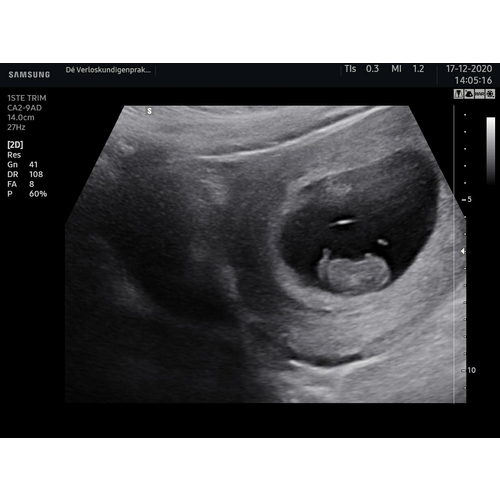

Ik dacht 8 weken te zijn bij de echo ze hadden me alleen iets terug gezet naar 7+4. Nu alweer een goede termijn echo gehad en vandaag alweer 11+4.

Ligt een beetje aan de verloskundige waar je zit. Bij de verloskundige waar ik bij zit is dit een medische echo. De vitaliteits echo. Waar ze kijken of er een gezonde zwangerschap is en of het een een of een meerling is. Dit doen ze vaak tussen de 7 en 9 weken.

Helaas moeilijk tezien gisteren echo gehad ban 8+5 maar mijn baarmoeder ligt nog wat verder naar achter dus niet zn hele helderen echo maar hartje klopt en alles was goed 😍😍